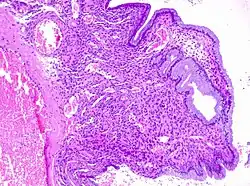

Cervical polyps can be seen during a pelvic examination as red or purple projections from the cervical canal.[4] Diagnosis can be confirmed by a cervical biopsy which will reveal the nature of the cells present.[4]

Structure

Cervical polyps are finger-like growths, generally less than 1 cm in diameter.[4][5] They are generally bright red in colour, with a spongy texture.[3] They may be attached to the cervix by a stalk (pedunculated) and occasionally prolapse into the vagina where they can be mistaken for endometrial polyps or submucosal fibroids.[5]